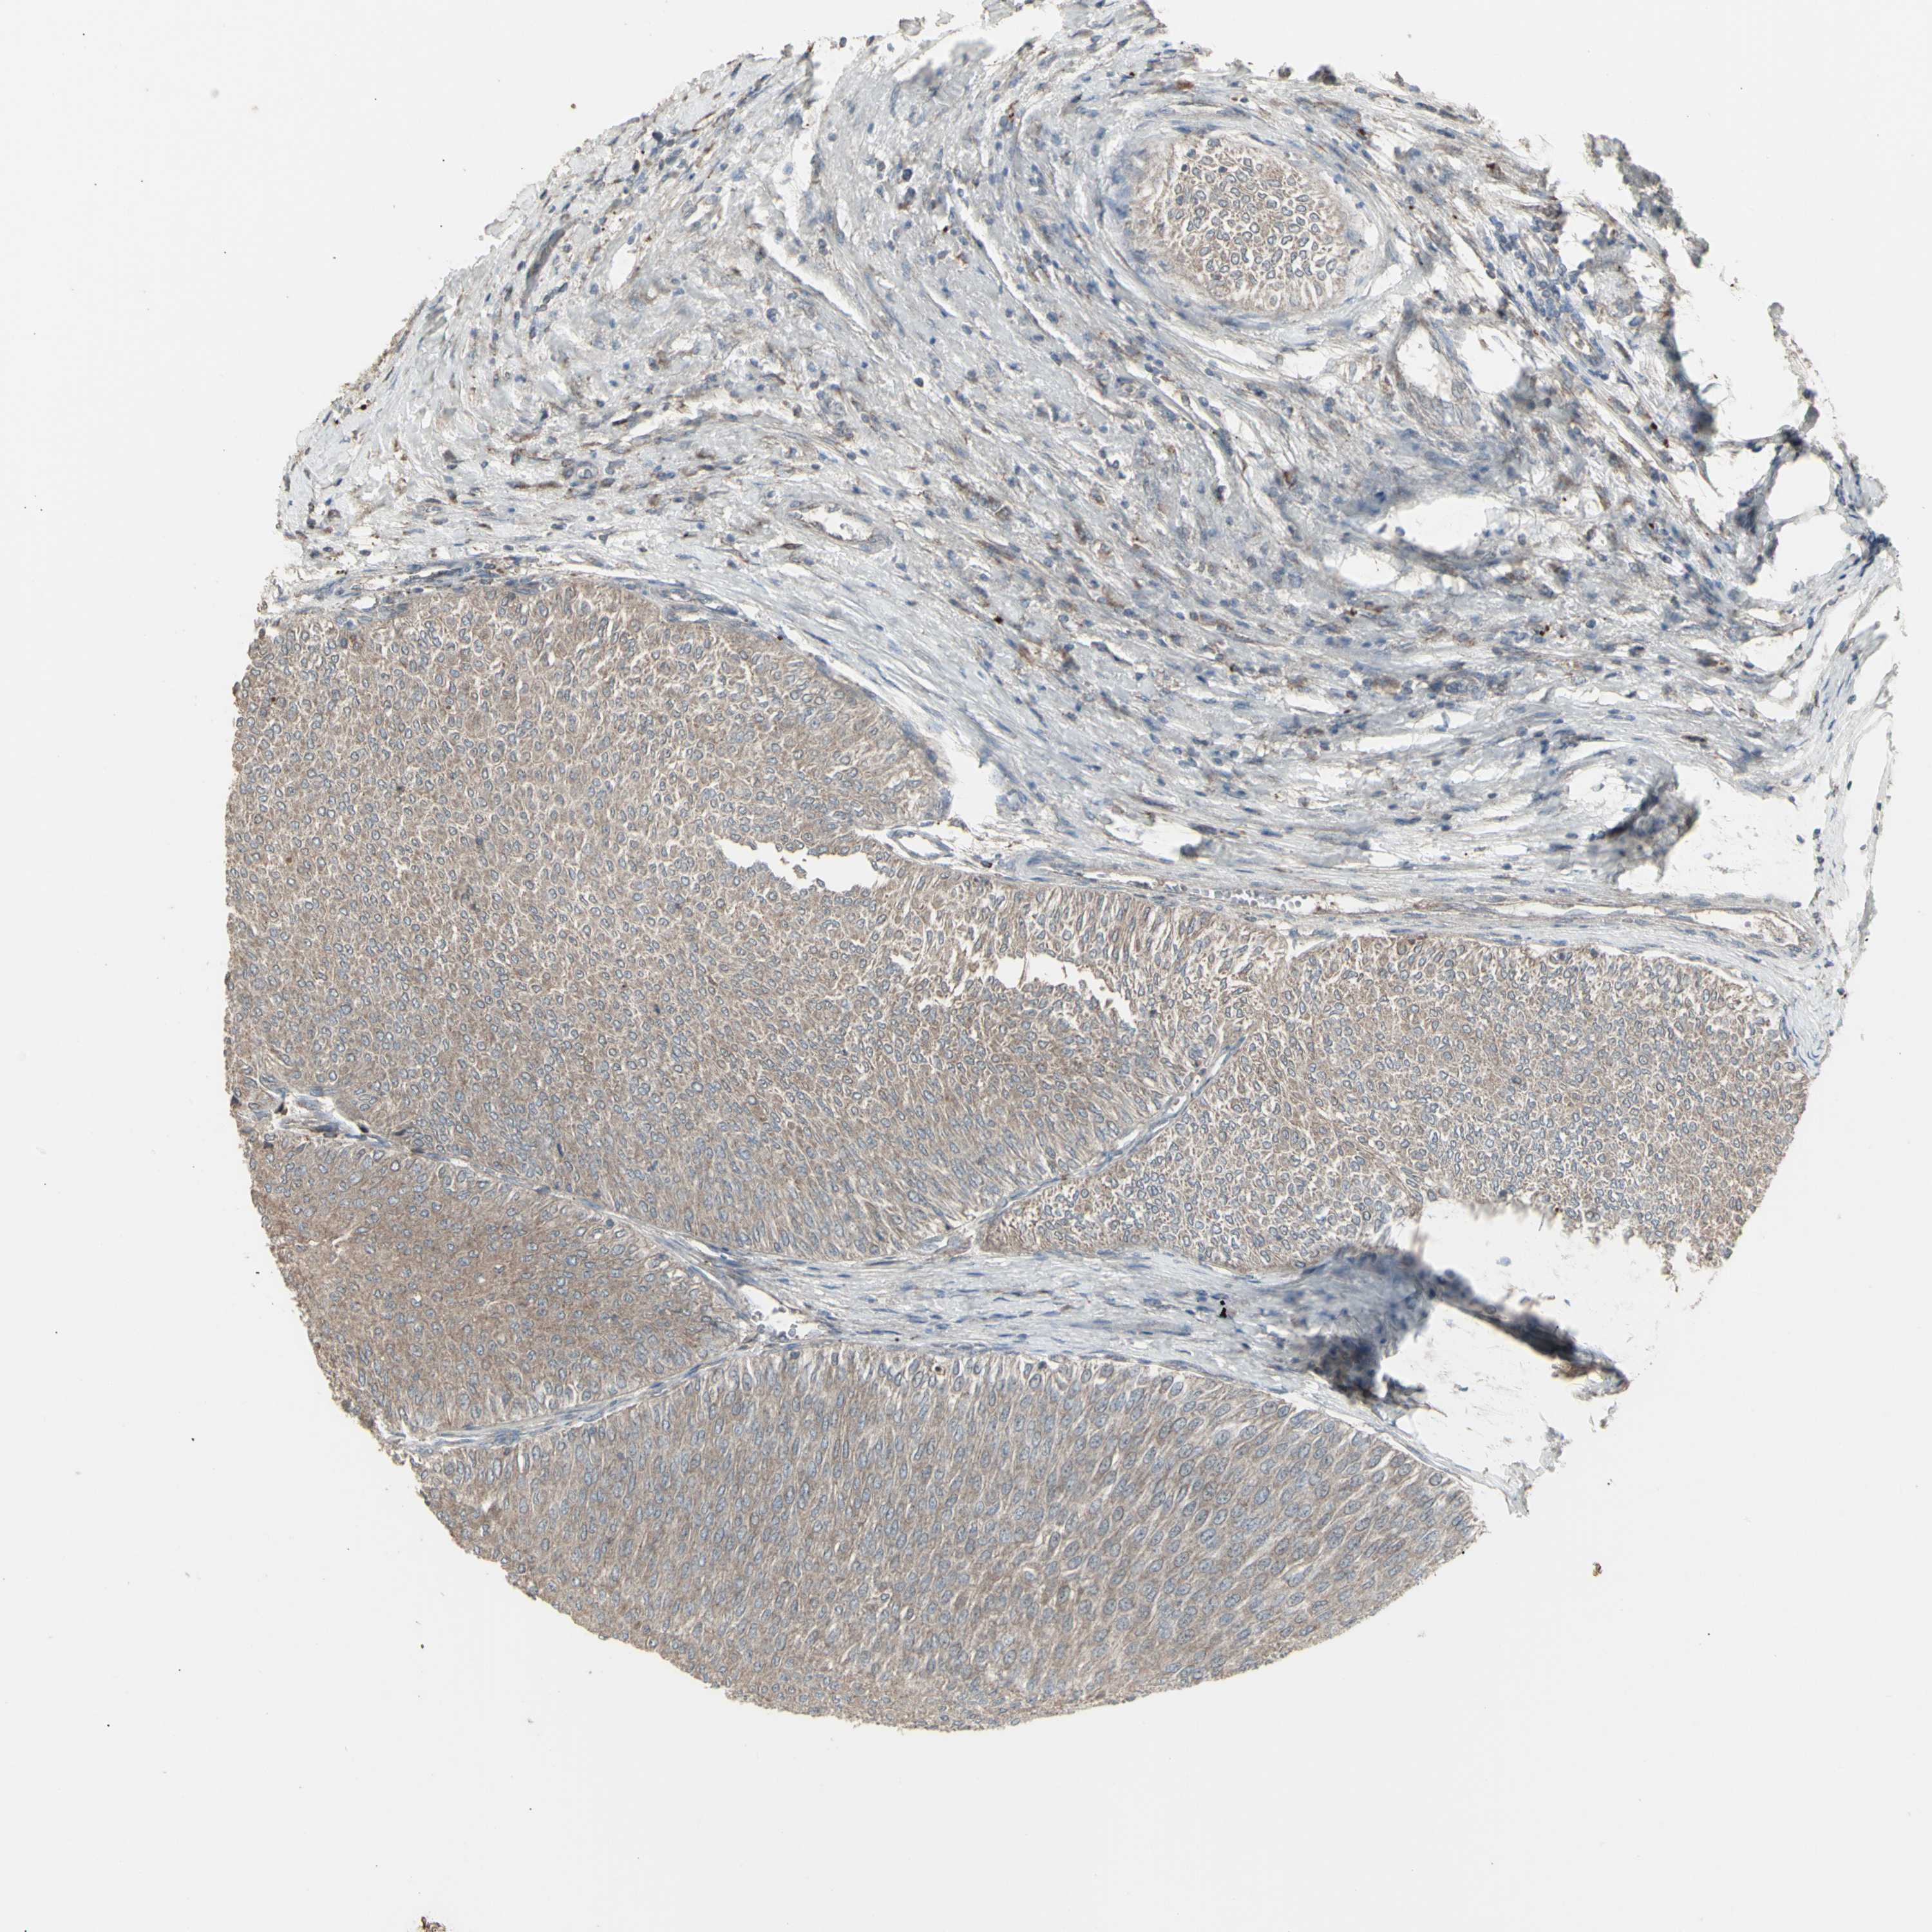

UROTHELIAL CANCER - Protein expressioni

A mouse-over function shows sample information and annotation data. Click on an image to view it in a full screen mode. Samples can be filtered based on level of antibody staining by selecting one or several of the following categories: high, medium, low and not detected. The assay and annotation is described here.

Antibody stainingi

Antibody staining in the annotated cell types in the current human tissue is reported as not detected, low, medium, or high, based on conventional immunohistochemistry profiling in selected tissues. This score is based on the combination of the staining intensity and fraction of stained cells.

Each image is clickable and will lead to virtual microscopy that enables deeper exploration of all samples and also displays staining intensity scores, fraction scores and subcellular localization as well as patient and tissue information for each sample.

Antibody HPA002633

Antibody HPA046758

Antibody CAB010906

Staining

High

Medium

Low

Not detected

Intensity

Strong

Moderate

Weak

Negative

Quantity

>75%

75%-25%

<25%

None

Location

Nuclear

Cytoplasmic/membranous

Cytoplasmic/membranous,nuclear

Urothelial carcinoma, High grade

Urothelial carcinoma, Low grade